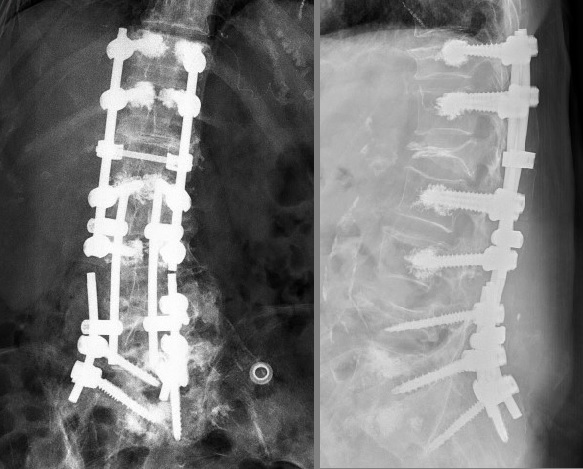

BT Görüntüsü

Resim 5: BT'de her iki L5 vidasının inferiordan ve sağdakinin ayrıca medialden gittiği, iki yanda L5-S1 nöral foramene ve sağda kanala girdiği, S1 vidalarının gevşeyerek S1-S2 korpuslarında derin kaviteler açtığı ve sağda S1 vidasının rod üzerinde tamamen dönerek karşıya uzandığı görülmekte. L4 korpusu yüksekliğini tamamen kaybetmiştir.

Metal artefaktlı MRG

Resim 6: Yoğun metal artefaktı MR değerlendirmesini olanaksız kılmaktadır. Sakral bölgede yaygın sıvı görüntüsü vardır (hematom? BOS?).